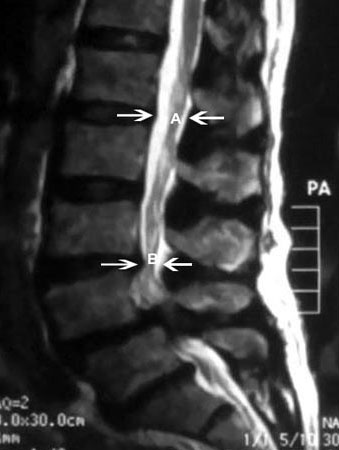

სპინალური სტენოზის მაგნიტურ-რეზონანსული გამოკვლევა: (A) შემოსაზღვრავს სპინალური არხის ნორმალურ საგიტალურ დიამეტრს. (B) შემოსაზღვრავს სპინალური არხის მძიმე შევიწროვებას

ექიმ Dr K. Singh საკუთრება; გამოყენებულია ნებართვით